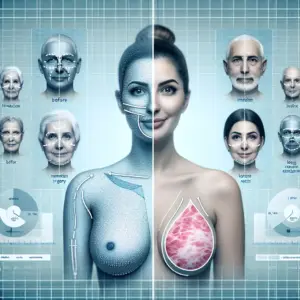

A melhor cirurgia para levantar as mamas varia conforme o grau de ptose, volume e pele, com técnicas específicas para cada caso. Avaliação médica personalizada é essencial para resultados naturais e satisfatórios.